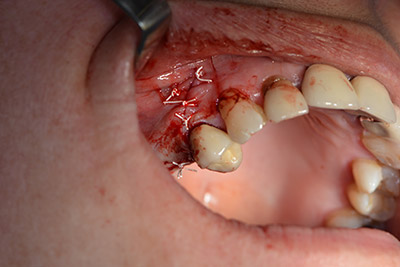

Имплантът е поставен и костта е изградена. В този случай, поради големината на зоната за аугментация, автогенните костни парченца, събрани с костен сондаж след имплантирането в зона 16 и фенестрацията в зона 14, са смесени с костозаместващ материал.

Използвана е абсорбираща мембрана като бариера на букалната страна и покритие на аугментацията. Накрая са поставени устойчиви на слюнка конци (Фиг. 15 до 19).